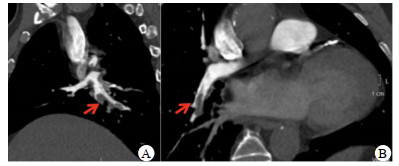

术后胸痛症状缓解,但喘憋,呼吸困难不能缓解。术后查体:脉搏90~100次/min,血压110~120/70 mmHg,呼吸频率30次/min,经皮指氧饱和度为80%。右肺呼吸音稍弱,未闻及干湿啰音,心界不大,心率90~100次/min,律齐,各瓣膜区未闻及杂音。腹软,无压痛,反跳痛,肝脾肋下未触及,肠鸣音5次/min。术后复查心电图:前壁导联ST段回落。心脏超声示:心脏各腔大小形态正常,射血分数(ejection fraction, EF)45%,后间隔中上段、下壁中上段及左室后壁心肌运动减低。右室游离壁运动减低,三尖瓣环收缩期位移10 mm,瓣膜未见功能异常。实验室检查:凝血项D-二聚体7 700 ng/mL(参考值0~243 ng/mL),N末端B型利钠肽原(NT-proBNP)2 248 ng/L(参考值0~125 ng/L),高敏肌钙蛋白T(hs-cTnT)0.027 μg/L(参考值< 0.017 μg/L)。血气分析提示:pH 7.40,二氧化碳分压35.7 mmHg,氧分压75 mmHg。立即完善肺动脉血管成像示:右肺动脉主干远端可见充盈缺损,右下肺动脉可见充盈缺损,左上肺动脉近端可见充盈缺损(图 3)。双下肢静脉、双侧髂静脉和下腔静脉血管超声均未见明显充盈缺损,血管通畅。双上肢动静脉和双侧锁骨下动静脉超声均未见充盈缺损,血管通畅。

| A纵切面可见右下肺动脉血栓,B横切面可见左肺动脉血栓;右肺动脉主干远端可见充盈缺损,右下肺动脉可见充盈缺损,左上肺动脉近端可见充盈缺损 图 3 患者肺动脉造影 |